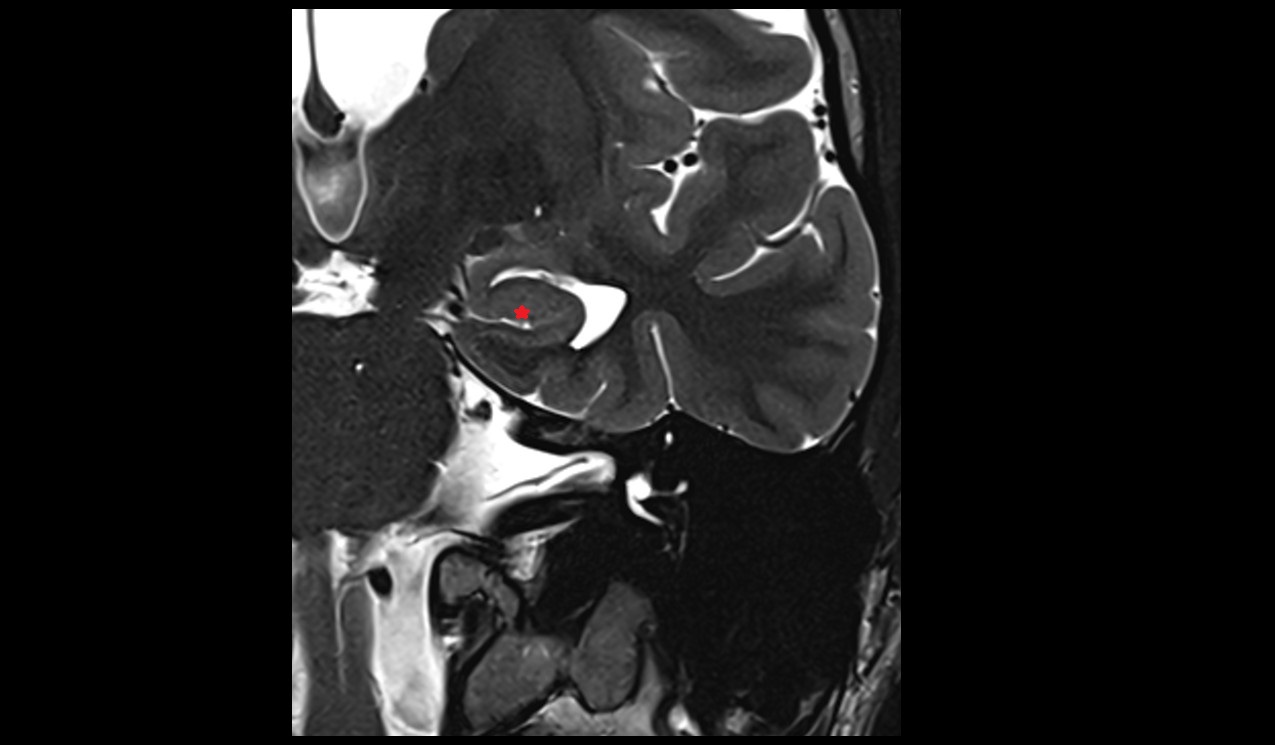

- Fetal brain

- Fetal caudate nucleus

- Fetal thalamus

- Fetal pons

- Fetal cerebellum

- Fetal occipital lobe

- Fetal temporal lobe

- Fetal parietal lobe

- Fetal frontal lobe

- Fetal third ventricle

- Fetal fourth ventricle

- Fetal lateral ventricle

- Fetal superior sagittal sinus

- Fetal straight sinus

- Fetal transverse sinus

- Fetal sigmoid sinus

- Medial tibial plateau